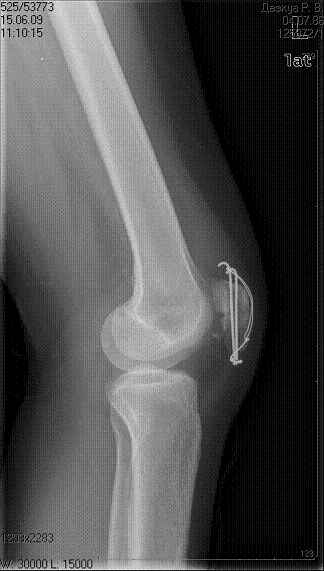

Цифровые  картиники это примерно 3,5  недели  посе  операции,

Вложение не в текстовом формате было извлечено…

Имя     : 15.06.0903 3,5 недели  после операции (2).jpg

Тип     : image/jpeg

Размер  : 13989 байтов

Описание: отсутствует

Url     : http://weborto.net:8080/pipermail/ortho/attachments/20090710/17fd1643/attachment-0007.jpg